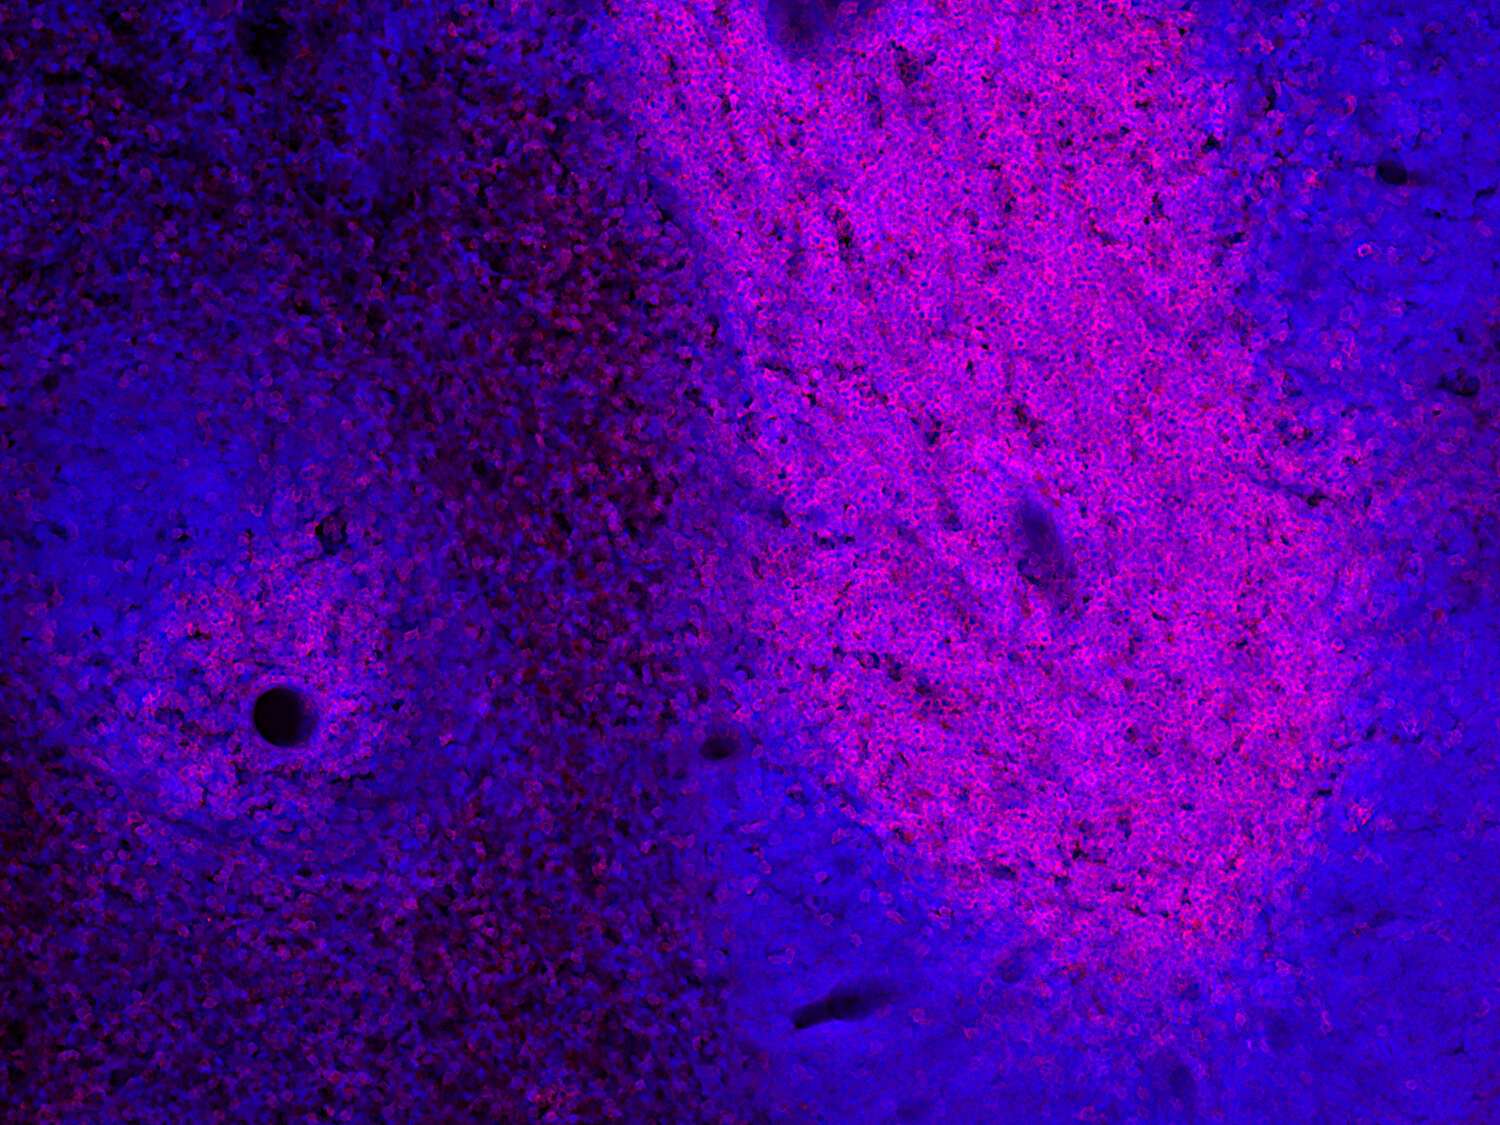

IHC: 1 : 100 gallery

IHC-P: 1 : 100 gallery

Immunohistochemistry (IHC) on 4% PFA perfusion fixed tissue with 24h PFA post fixation. Immunoreactivity is usually revealed by fluorescence or a chromogenic substrate. Some antibodies require special fixation methods or antigen retrieval steps. For details, please refer to the ”Remarks” section.

IHC: Antigen retrieval with citrate buffer pH 6 is required.